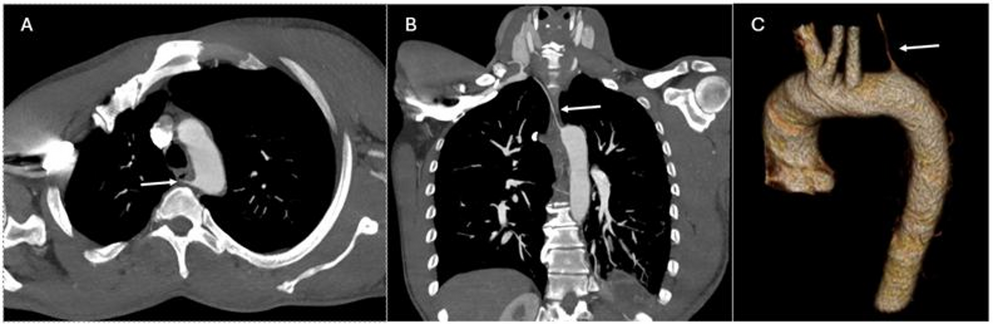

Left aortic arch with aberrant right vertebral artery

Competing interests The authors declare no competing interests. ...

International Journal Of Cardiovascular Imaging